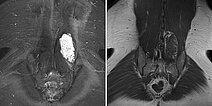

In der dynamischen, konstrastmittelunterstützten MR-Angiographie (hier Spätphase über 2 min nach i.v. Kontrastmittelgabe, links koronare und rechts sagittale Rekonstruktion) zeigt die Läsion keine Kontrastmittelanreicherung oder vermehrte Vaskularisation. Sie ist praktisch nicht sichtbar.

Es wird unmittelbar anschließend eine sonographisch gesteuerte Stanzbiopsie mit einer dünnen 16-Gauge-Biopsienadel durchgeführt. Nur geringe Blutung bei der Nadelbiopsie, die durch Kompression schnell gestillt wird. Beachte das gewonnene dunkelrote Gewebestückchen, das makroskopisch fast wie Blut aussieht, aber aus den blutgefüllten, dysplastischen Hohlräumen der venösen Malformation besteht.